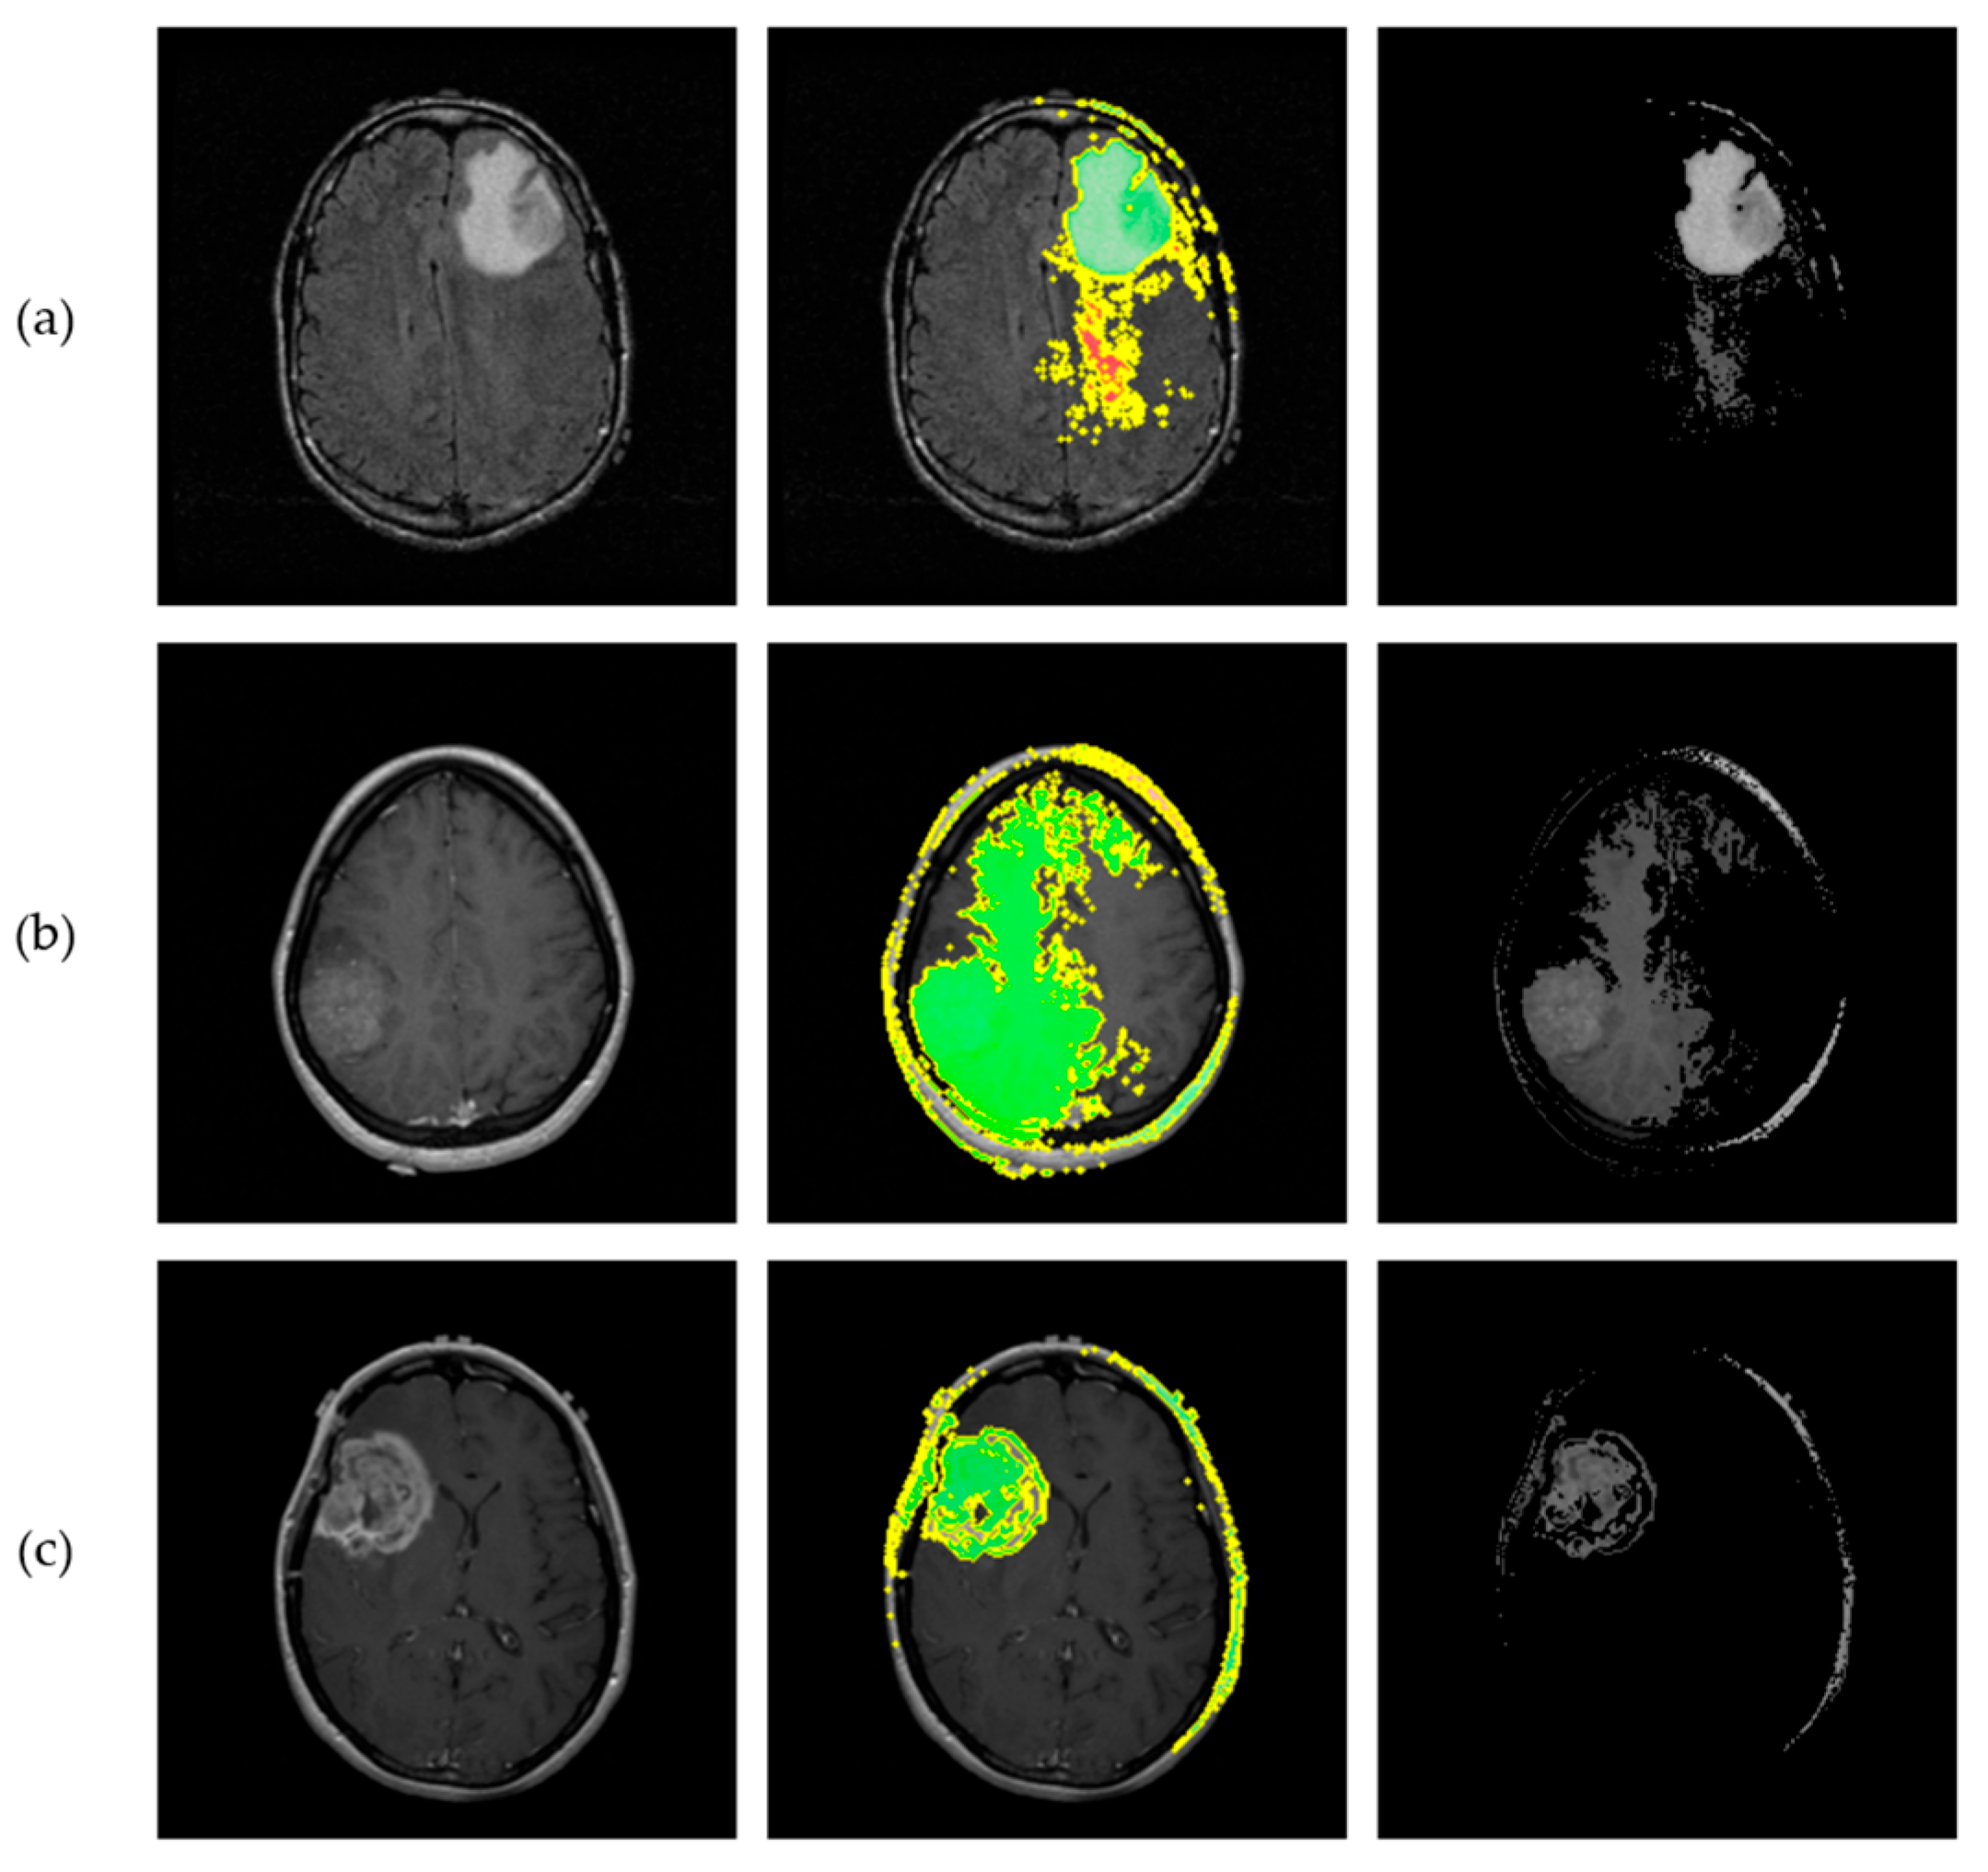

2.5. Explainable AI Methods

3.5. Explainable AI Insights